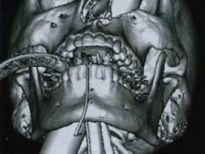

Şoke eden röntgen filmleri

Bu röntgen filmleri görenleri şaşkına çeviriyor!